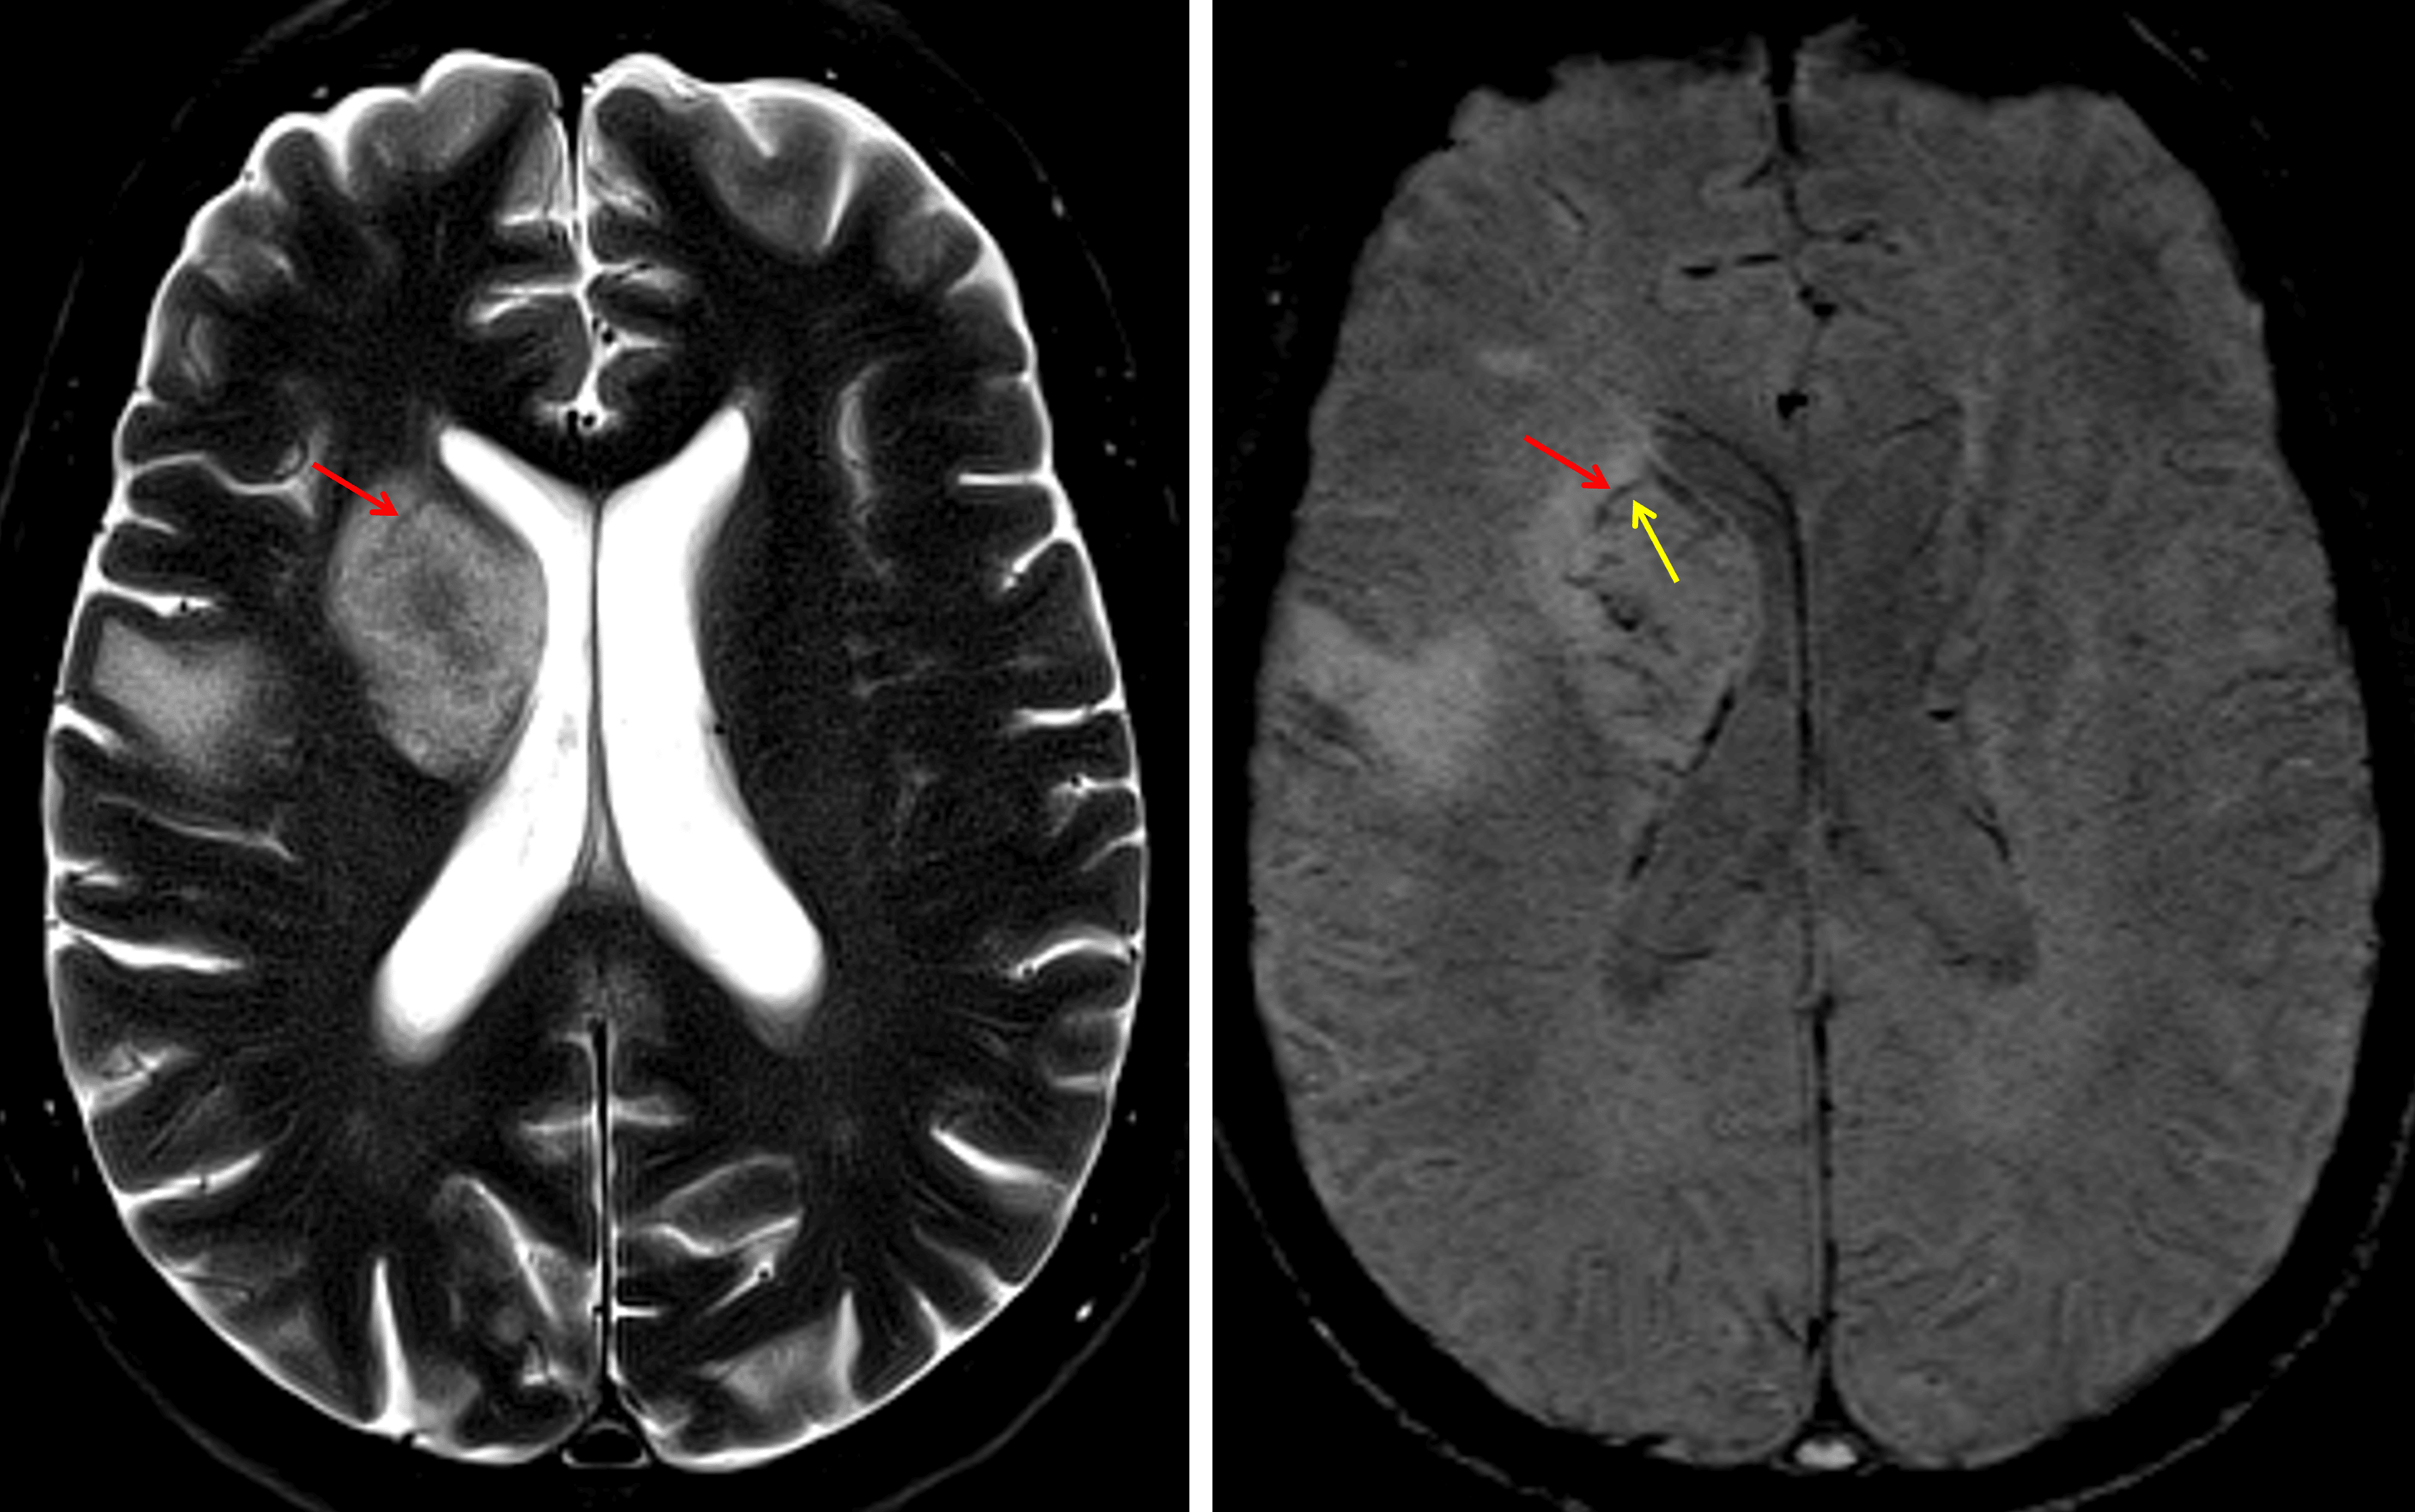

Although this case is not the best example of an abscess rim, there is a thin T2 and SWI hypointense rim (red arrows) with a thin internal SWI hyperintense ring (yellow arrow).